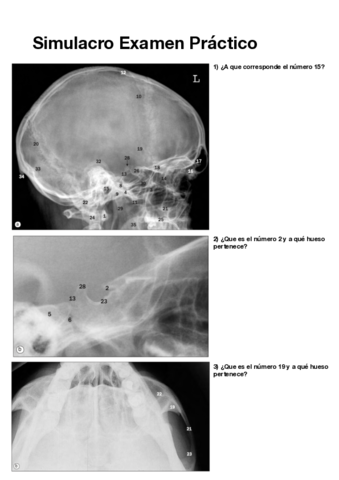

Apuntes - Simulacro-Examen-Practico-pdf.pdf

6 páginas